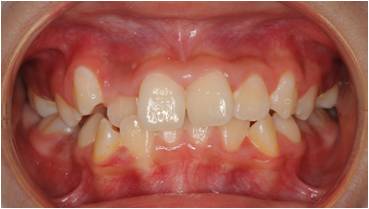

治療前

乱ぐい歯の小児矯正治療(10歳の女子)の治療前後の写真です。矯正治療によって前歯の強い叢生(ガタガタ)・ねじれが大幅に改善され、咬合関係も良好になりました。

| 年齢・性別 | 10歳 女子 |

| 矯正治療期間 | 約1年6ヵ月 |

| 治療回数 | 11回 |

| 治療費 | 40万円程度(税込) |

| 抜歯の有無 | 無し |

| 使用矯正装置 | マルチブラケット装置 |